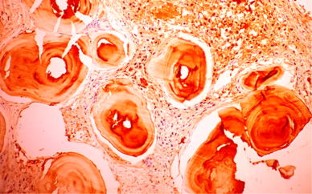

Primary localized amyloidosis in the head and neck region is a rare entity. The most commonly involved organ is larynx. Primary amyloidosis localized to the sinonasal tract is extremely rare. We report one such case along with a brief review of the associated literature. The aim of reporting this case is to emphasize the fact that sometimes nasal amyloidosis can also present with signs and symptoms of nasal and nasopharyngeal malignancy. The definitive diagnosis in such cases depends upon histopathology and further confirmed by immunohistochemistry. A 55-year old male presented with recurrent episodes of nasal bleed, bilateral nasal obstruction, and bilateral hearing loss from last 7 years. On clinical examination a mass was found in the nasal cavity on both sides reaching up to the nasopharynx. Contrast enhanced CT scan revealed that the mass was extending up to the skull base and destroying bony landmarks of the nasal cavity and paranasal sinuses. Mass was proved to be amyloidosis after histopathological examination. It showed multiple blotches of globular submucosal deposit of amyloid, on staining with Congo red. Immunohistochemistry confirmed AL amyloidosis with expression of mixed kappa and lambda light chain immunoglobulin (κ > λ). No evidence of systemic amyloidosis was found after proper work up. It was managed by conservative surgery.